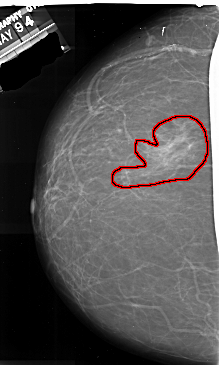

FILE: A_1014_1.LEFT_CC.OVERLAY

TOTAL_ABNORMALITIES 1

ABNORMALITY 1

LESION_TYPE MASS SHAPE IRREGULAR MARGINS ILL_DEFINED

ASSESSMENT 4

SUBTLETY 4

PATHOLOGY MALIGNANT

TOTAL_OUTLINES 1

BOUNDARY

LEFT_CC LINES 6931 PIXELS_PER_LINE 4156 BITS_PER_PIXEL 16 RESOLUTION 42 OVERLAY